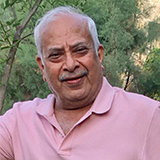

Raj Rani 72 years lady suffering from pain in the both knees from last 10 yrs with severe limitations of activities . She was almost bedridden for the last 2 yrs. She was found to be having osteoarthritis of the both knees resulting in “Severe Varus ”deformity with bone loss.